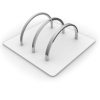

Корректор класса II Вильямса (исполнение 3) - Набор 320-0100

Описание товара

Характеристики